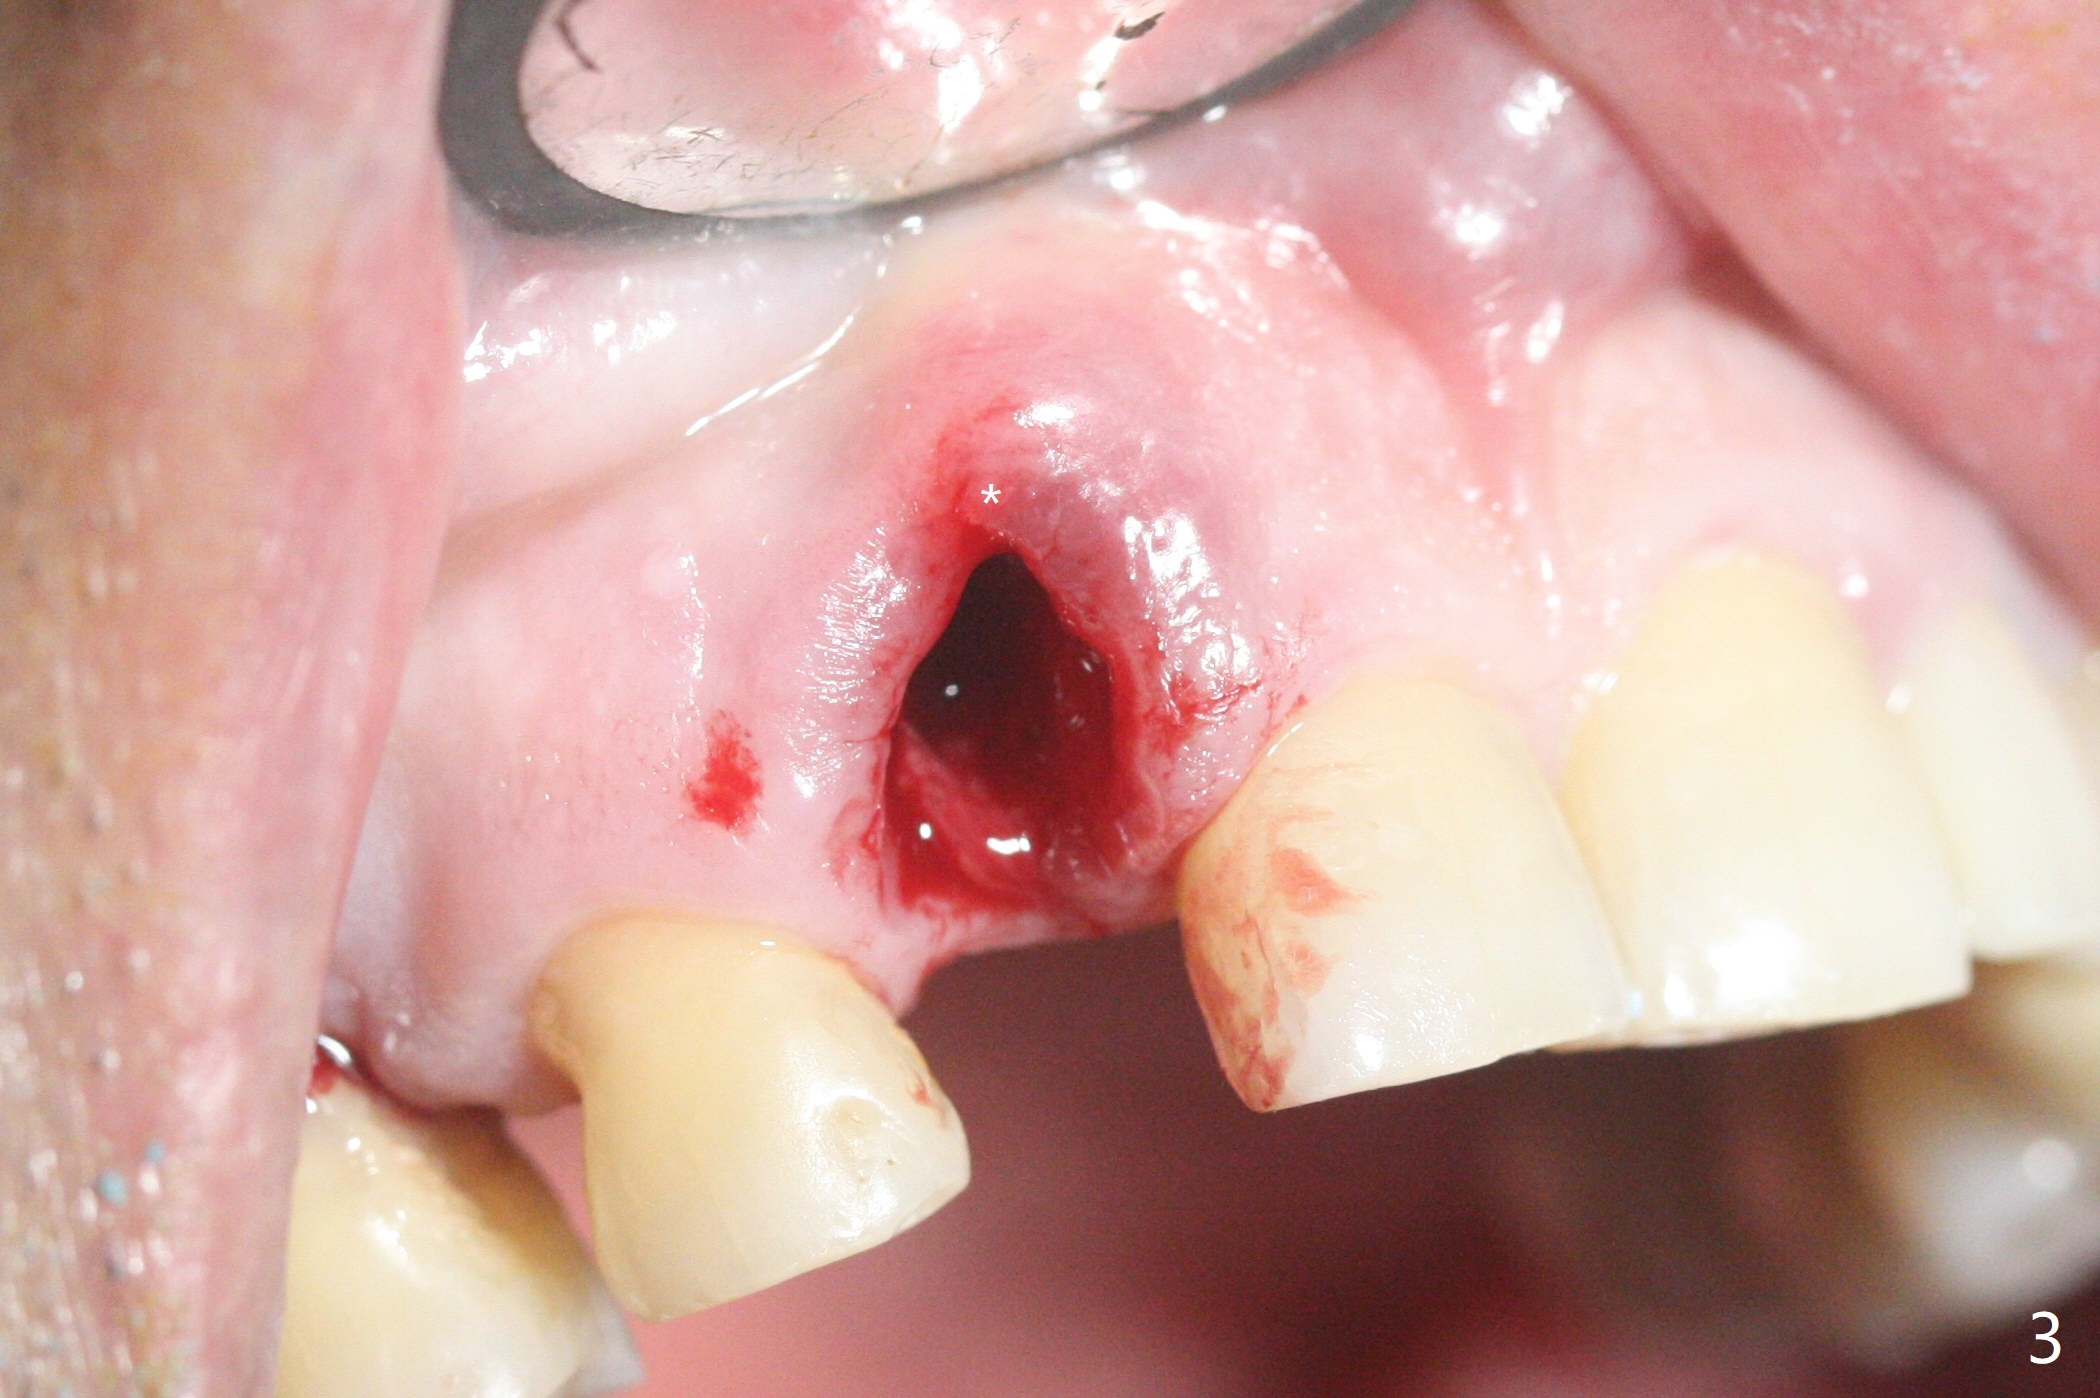

68岁男士右上2严重骨质吸收,颊侧骨板缺失,术前牙龈退缩也十分明显(图一,二),术中对脆弱牙龈缘(图三:*)不应施加任何压力或者牵拉,更不能切开,保持最佳血供。按照术前设计,在牙槽窝腭侧钻洞(图四),植入2.5x15毫米一段式植体(扭力>35Ncm),基台特长(牙龈厚,图五)),基台位于合适修复位置(图六),4-5毫米螺纹颊侧暴露(图七:*)。植骨(图八(CT冠状切面(拔牙后:黑色)):箭头)前,将PRF膜(白线)一头(a)插入牙槽窝颊侧,另外一头(图八,九:b)放置颊侧牙龈颊侧。然后填入粘性骨粉(图九:S;图十四:*),将b头PRF膜往下翻,它末端事先冲一个洞(punch a hole using sterilized rubber dam punch),插入基台(图十(粉红色),十一),这样PRF膜不移位,牢靠地固定骨粉(图十(红圆圈),图十四:*),最后使用树脂敷料覆盖伤口(图十二,十三:A),同样需要基台(箭头,也就是一段式植体)固定,也就是没有即刻植体,就没有骨粉固位。术后两个月伤口缩小,肉芽组织生长(图十五)。撤除树脂敷料后,制作临时牙冠,半个月后唇侧植体有些暴露(图十六),嘱咐强化口腔卫生。